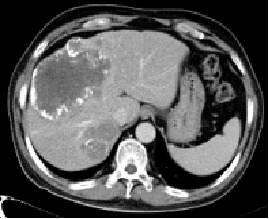

影像学检查:

2014-09-26CT:

CT未见明确肿瘤组织强化,拟采用MRI随访

2014-10-24MR:

增强MRI提示病灶边缘少许强化,考虑仍有活性